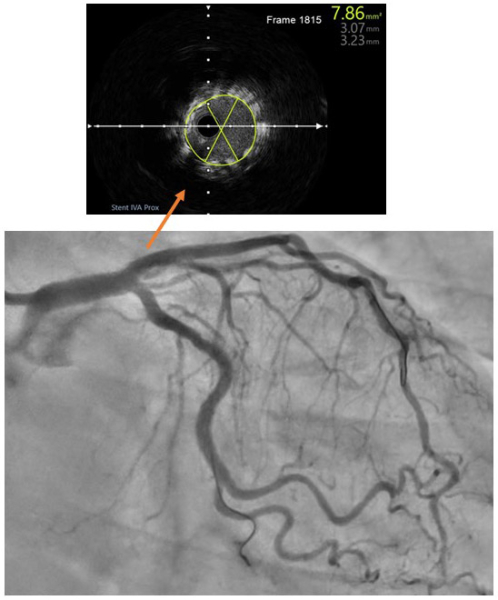

L’angiographie finale (Vidéo 3) avec contrôle IVUS (Figure 5) permet de s’assurer la bonne apposition, la bonne expansion du stent sur toute la longueur ainsi que l’absence de dissection iatrogène.

Figure 5 : extrait du run final d’IVUS post angioplastie

- Contrôle post angioplastie. Après une procédure complexe, l’imagerie endocoronaire post angioplastie permet essentiellement d’éliminer une dissection iatrogène, une sous-expansion (obtention d’une Minimum Stent Area -MSA- maximale, un bon indicateur de morbi mortalité au long cours [14]) et de contrôler l’apposition du stent (Figure 6). En cas de traitement de bifurcation, l'imagerie endocoronaire peut également évaluer la position du guide de la branche fille après le refranchissement des mailles, afin de s'assurer de sa position intrastent dans la portion proximale. Il permet également d’évaluer la maladie résiduelle sur le reste du vaisseau avec exclusion de "geographic miss" correspondant à la présence de sténose résiduelle de bord.